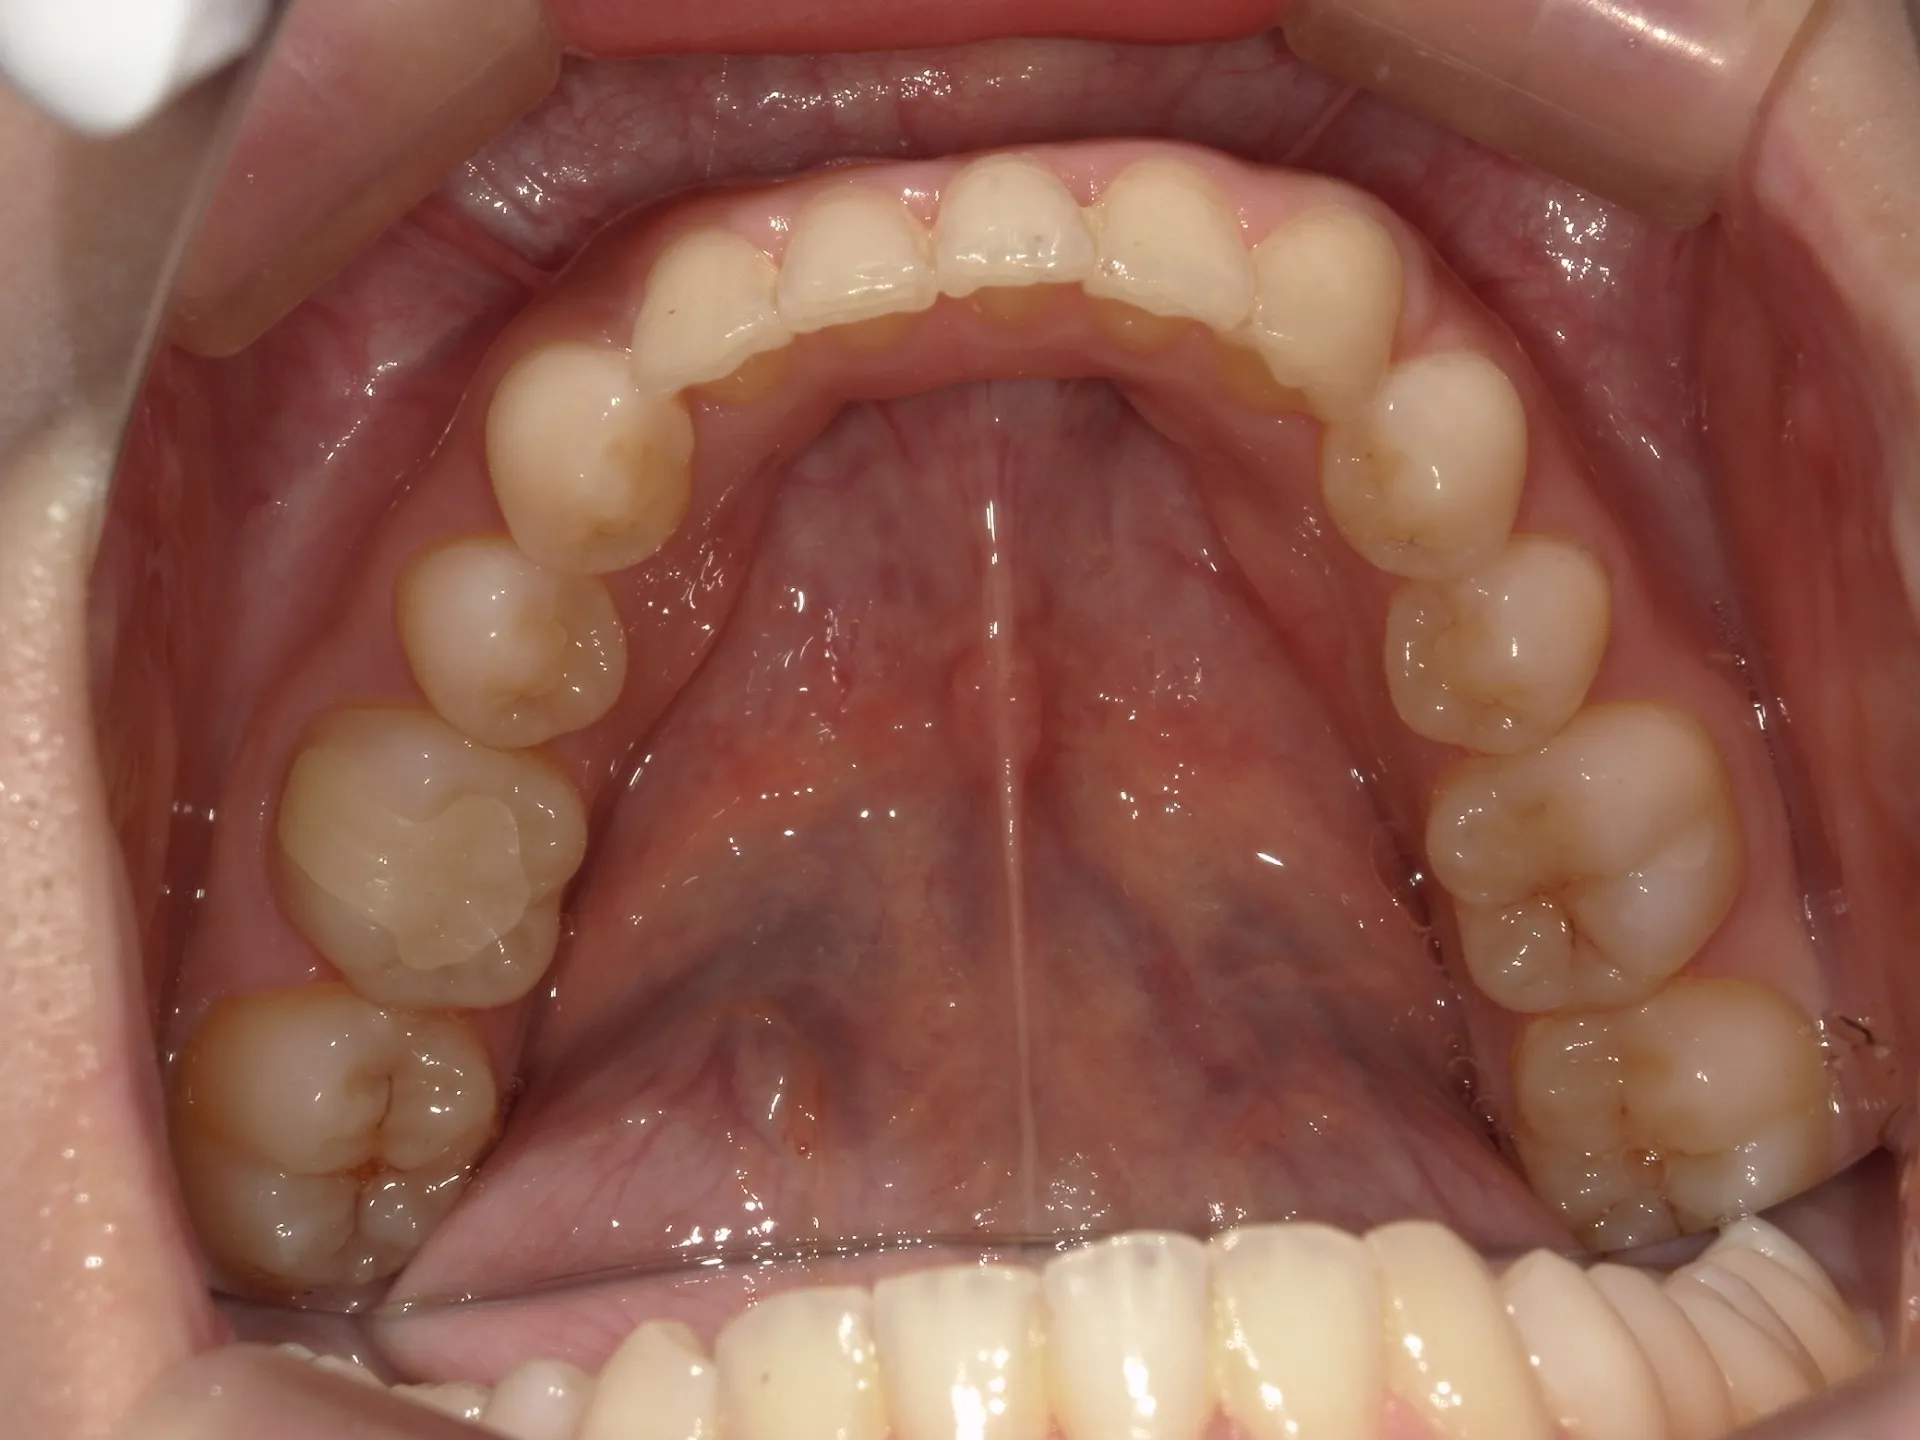

大きく飛び出してしまった前歯の矯正と変色の治療を希望された症例をご紹介いたします。